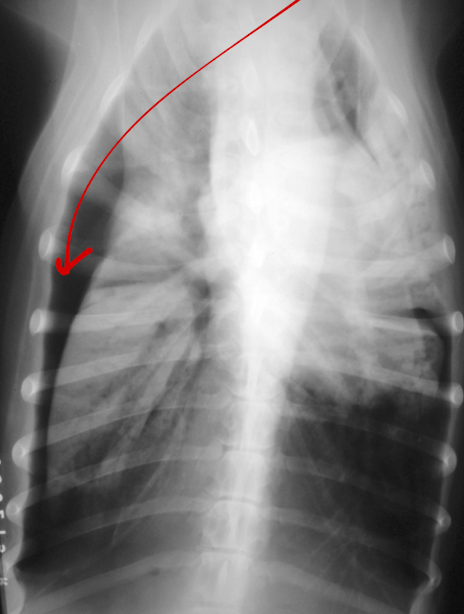

What is the arrow pointing to?

intra-capsular swelling